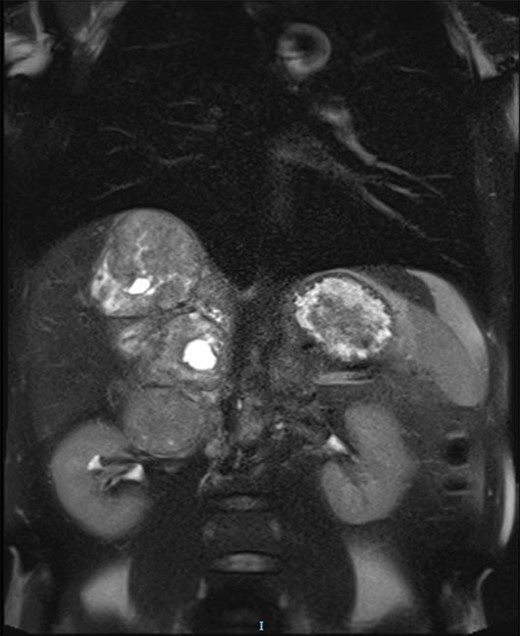

The magnetic resonance imaging (MRI) found the mass, which was measured at 85 × 60 × 160 mm, heterogeneous, with isointense and T1-weighted hyposignal (Fig. 2), isointense and T2-weighted hypersignal (Figs 3 and 4), and diffusion-weighted heterogeneous hypersignal. After injection of the contrast product, the mass did not appear to be hypervascular, and uptake was more pronounced in the late phase, indicative of a fibrous nature. The FDG-PET scan showed a hypermetabolic mass with SUVmax of 6.3. Finally, after excess secretion of catecholamines had been ruled out, a CT-guided biopsy was performed, with the histological analysis concluding that a schwannoma was highly probable.